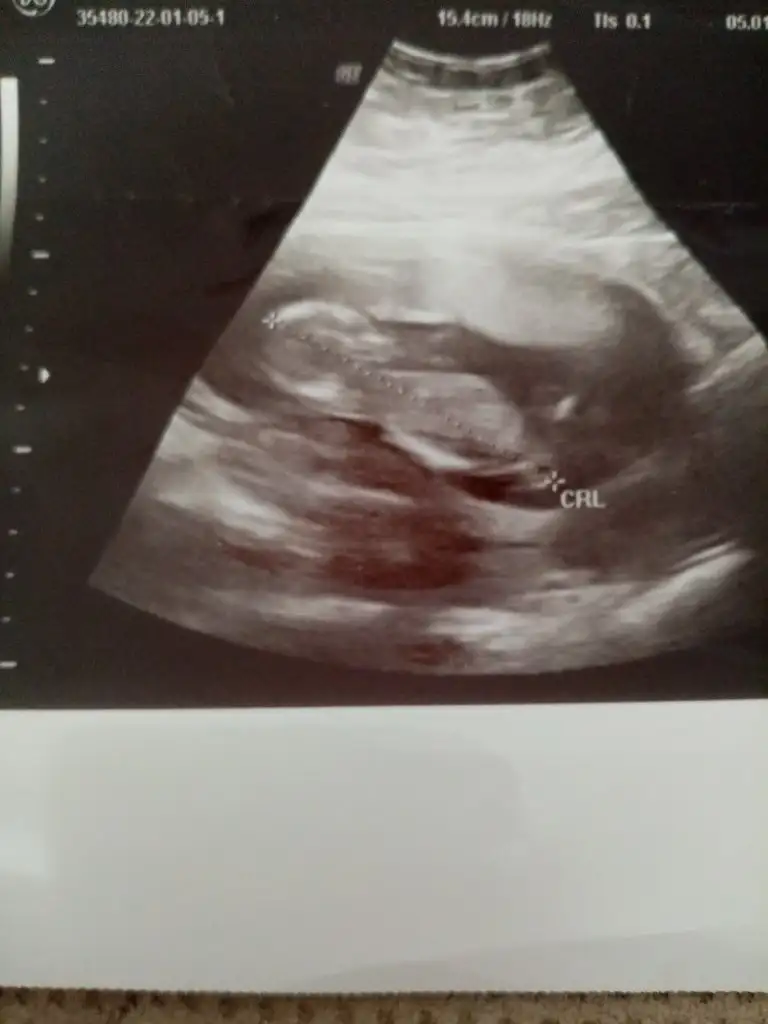

Emin olmadım kız gibi sankiIkra meyra bana da cinsiyet tahmini yaparmisiniz